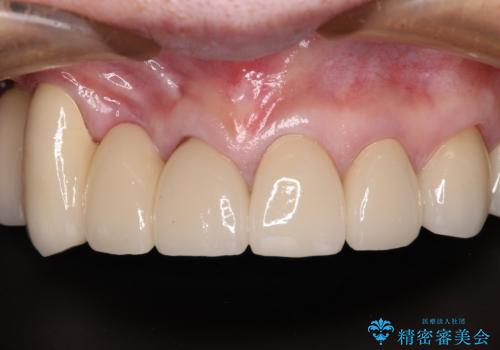

治療途中で放置してしまった前歯 オールセラミッククラウンによる補綴治療

前歯部については抜歯が必要な歯を抜歯し、インプラントやブリッジなどにより補綴治療を行うこととしました。

臼歯部は今後抜歯が必要となった際に、インプラントにより咬合を構築していくこととしました。今回の治療においても、今後の臼歯部の治療に対応できるよう治療計画を立案しています。